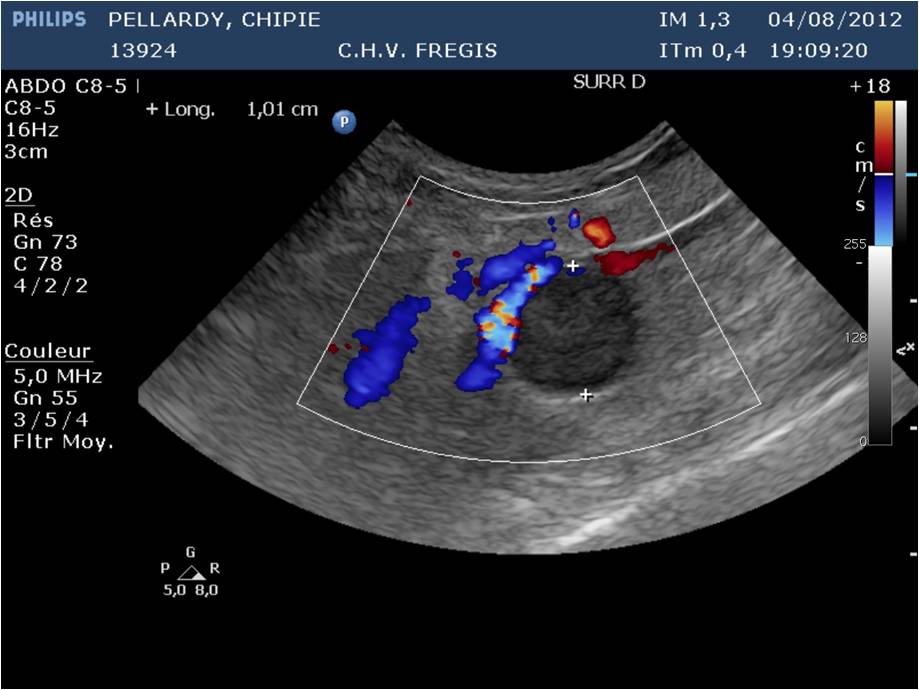

Lorsque les glandes surrénales sont fortement stimulées, elles deviennent progressivement hyperplasiques puis tumorales (tumeur bénigne puis maligne). Le diagnostic peut être établi par échographie, réalisée par un vétérinaire expérimenté avec les furets, et par une prise de sang (dosage des hormones en question). Suivant l'extension et la présence ou non d'embole vasculaire, il est recommandé de poser un implant hormonal ou de réaliser une surrénalectomie. Cette chirurgie est particulièrement risquée à cause de la proximité des glandes surrénales avec l'aorte, un vaisseau sanguin vital pour l'organisme. Il peut être utile d'utiliser des outils de microchirurgie ainsi que du matériel de pointe tel qu'une caméra endoscopique per-opératoire Vitum pour maximiser la réussite de la chirurgie.